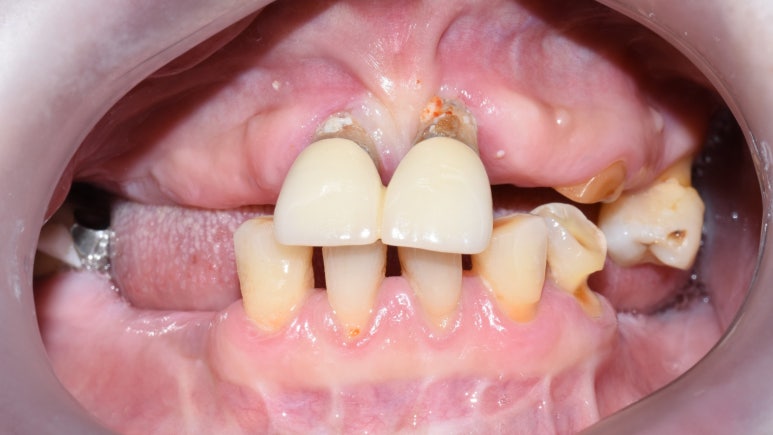

- 기초 수급자 환자 흔들리는 위 치아 빼고 위 전체 틀니,

아래쪽 어금니는 씹을 수 있게 최소 개수의 임플란트

- 상악 전체임플란트, 하악어금니 없는 부분 임플란트

상악 흔들리는 브릿지와 치아 발치 후 상악전체 임플란트

↓

상악 전체 임플란트 후

- 상악 전체임플란트 및 하악 어금니 없는 부위 임플란트